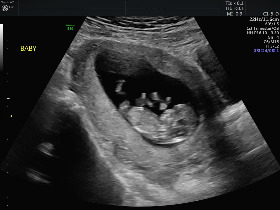

Image_7.jpg

KakaoTalk_Photo_2019-09-11-10-04-03.jpeg

좌) 12주 초음파 사진인데, 네 팔다리를 다 동원해서 발버둥을 치더군요...... 우) 한국에서 처음으로 해봤던 테스터기 인증입니다.